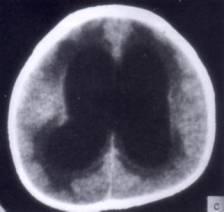

病历摘要:??患者女性,10岁。结核性脑膜炎愈后8月,头痛伴恶心呕吐1周,并渐加重。体检:神清,精神差,反应迟钝,双眼底视神经乳头水肿,双眼外展差,余未见...

问题 病历摘要:??患者女性,10岁。结核性脑膜炎愈后8月,头痛伴恶心呕吐1周,并渐加重。体检:神清,精神差,反应迟钝,双眼底视神经乳头水肿,双眼外展差,余未见明显异常。 目前治疗脑积水的措施包括下列哪些?

选项 A.侧脑室-枕大池分流术 B.终板造瘘术 C.侧脑室-腹腔分流术 D.侧脑室-右心房分流术 E.侧脑室-颈静脉分流术 F.腰椎蛛网膜下腔-腹腔分流术 G.应用醋氮酰胺等药物